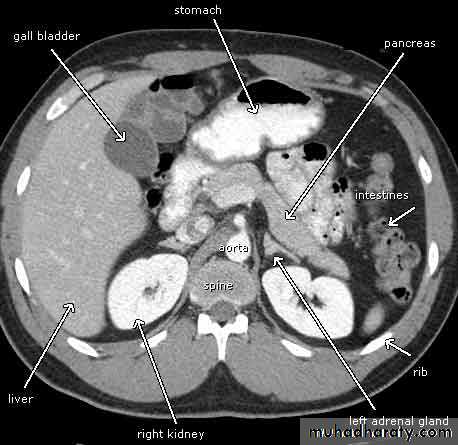

Normal CT scan of abdomen